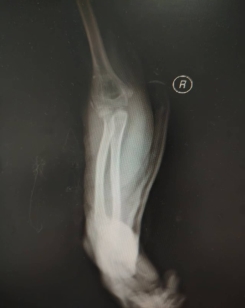

患儿,女,11岁,5月14日因“外伤后右肘肿痛1小时余”入院,术前X线提示右侧桡骨颈骨折,O’Brien分型Ⅱ型,入院后我科陈义权主任立即和张浩医生采用中医特色骨折夹板固定骨折处,于5月17日予右桡骨颈骨折闭合复位弹性髓内钉内固定术,术中我科陈义权主任采用Metaizeau技术,在腕部做一长约1cm切口,利用弹性髓内钉闭合复位骨折端。术后3月复查,骨折端基本愈合。我科成功将中医特色治疗与小儿骨折微创治疗技术完美结合。

图3、4:术中透视下X线